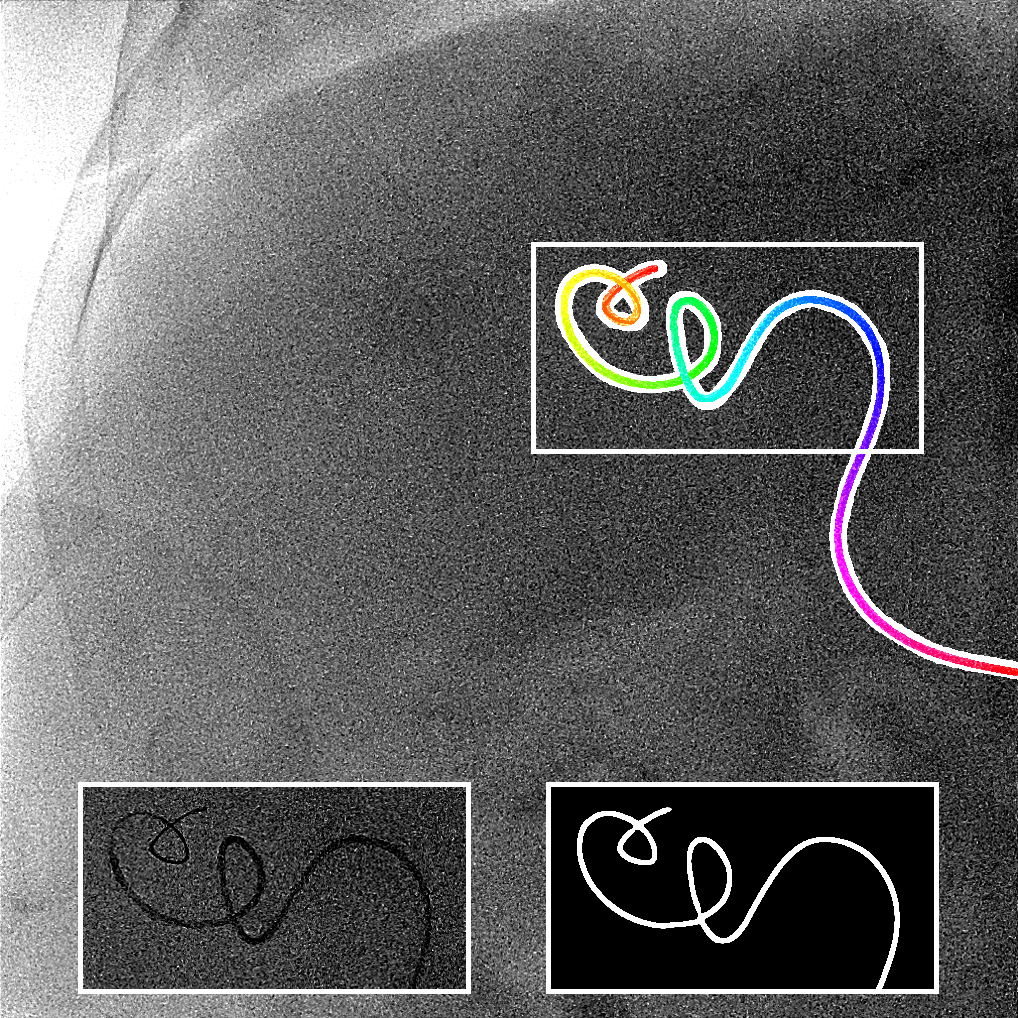

The output of the neural network is first thresholded with a threshold (between 0 and 1) and then skeletonized [19]. Next, the branches (ordered sets of pixels) are determined based on connectivity. Connection points are created between close branches. If the closest points between two branches are within a distance pixels, we consider this to be a possible connection, and there can be only one connection between two particular branches. Then, to link the branches, three steps are done (Fig. 2). First, for each connection, we divide and merge branches in order to have the longest branches. Second, loops are detected and merged following the direction at the crossing point. We have a loop in a branch when two points, within a distance pixels, have their distance along the branch of at least pixels. Before the third step, the first and second steps are repeated a second time with a distance superior to . Finally, in the last step, the remaining connected branches larger than pixels are considered as incomplete loops or straight loops due to foreshortening. We process them similarly as the second step by closing the two endpoints of their branch. When all the potential links have been processed, we keep the longest connected set of branches and choose amongst the two endpoints the farthest from the image border as the tip of the catheter centerline. Finally, the centerline is smoothed by fitting a spline.

We evaluate using the tip distance error (i.e. the distance between the annotated catheter tip and the tip of the segmented catheter), and the average distance between the manually segmented catheter and the automatically segmented catheter. Figure 3 shows the tip and catheter distances results. We compute the precision of the tip between consecutive frames. The median, average, minimum and maximum of the standard deviation per sequence of the tip distance error are respectively 0.7 mm, 4.9 mm, 0.1 mm and 55.7 mm. Five examples of segmentation are shown in Figure 4. In the third frame, the segmentation is going too far and follows part of the vertebrae. The fourth frame misses the proximal part of the catheter. The last frame is the only sequence with significant false positives. It is less noisy because it has been acquired with higher radiation dose. The neural network was not trained for such sequence.

Very few images have false positives after the CNN segmentation. Therefore, we can use simple criteria to extract the catheter centerline from the CNN segmentation. The results show that it works well and can handle self-intersections. The main problem in the extracted catheters are sometimes large gaps in the segmentation due to false negatives. As a consequence, occasionally the proximal part of the catheter is missing. With a larger training set, the model is expected to generalize better.